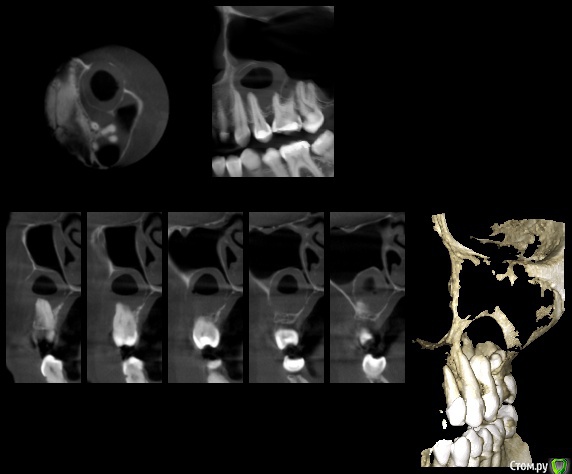

gum Опубликовано 6 ноября, 2016 Поделиться Опубликовано 6 ноября, 2016 Здравствуйте. Пациента еще не видел, клиники не знаю. Судя по КТ, четкие контуры, сохранение костного ободка и отсутствию 25 зуба, думаю что это резидуальная киста.Так ли это? Ссылка на комментарий

___49___ Опубликовано 7 ноября, 2016 Поделиться Опубликовано 7 ноября, 2016 (изменено) Кортикальная пластинка над 6 и 4 ыми зубами лизирована ? Биопсию не хотите предварительно взять ? Изменено 7 ноября, 2016 пользователем ___49___ Ссылка на комментарий

gum Опубликовано 8 ноября, 2016 Автор Поделиться Опубликовано 8 ноября, 2016 Кортикальной пластинки нет с вестибулярной стороны. Лечащий врач пациента сказал, что было обострение раскрыт 24 и получено гнойное отделяемое. 10.11 увижу пациентку, думаю без биопсии решить вопрос. Ссылка на комментарий

___49___ Опубликовано 8 ноября, 2016 Поделиться Опубликовано 8 ноября, 2016 Отпишитесь пожалуйста после оперативного вмешательства . Будите замещать дефект стенки верхнечелюстной пазухи ? если да то чем планируете это произвести ? и как - одномоментно или в два этапа ? Да похоже на разрастание оставшейся кисты от ранее удаленного 5 ого зуба . Интересна так же клиника и анамнез . Ссылка на комментарий